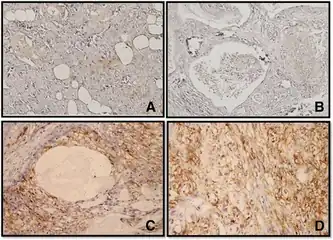

a-d)Immunohistochemistry for CD44 in Mucoepidermoid carcinomas

a-d)Immunohistochemistry for CD44 in Mucoepidermoid carcinomas -